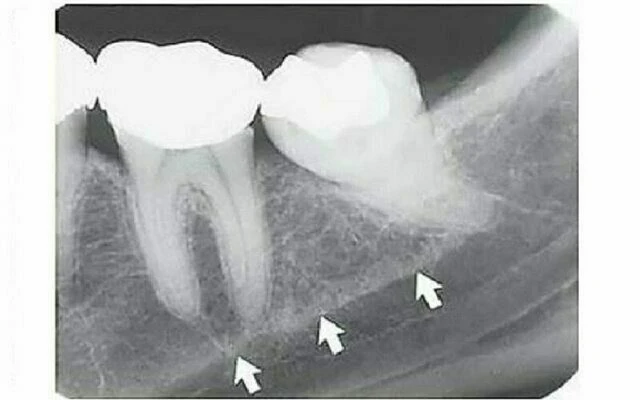

Ống dinh dưỡng

Ống dinh dưỡng chứa một bó thần kinh mạch máu và có hình ảnh dạng đường thấu quang với chiều rộng khá đồng đều. Chúng thường được thấy nhất ở phim quanh chóp ở hàm dưới chạy dọc từ phía dưới ống thần kinh xương ổ răng dưới đến một chóp răng hoặc vào khoảng giữa các răng cửa hàm dưới. Thấy được chúng trong khoảng 5% trường hợp trên tất cả bệnh nhân và thường ở người nam, da đen, người lớn tuổi và những người có huyết áp cao hoặc bệnh lý nha chu tiến triển. Chúng cũng cho thấy gờ xương mỏng, hữu ích khi đánh giá implant. Vì chúng có giải phẫu là khoảng trống bao quanh bởi thành là xương vỏ nên hình ảnh thường cho thấy biên giới xương dày. Đôi khi ống dinh dưỡng vuông góc với xương vỏ cho hình ảnh một vòng tròn thấu quang giống như hình ảnh thấu quang của bệnh lý. Gờ móng Gờ móng là một mào xương không đều nằm nên bề mặt trong của thân xương hàm dưới. Kéo dài từ vùng răng cối lớn thứ ba đến bờ dưới xương hàm dưới vùng cằm, nó đóng vai trò là chỗ bám của cơ hàm móng. Hình ảnh X quang chạy theo chiều nghiêng xuống và ra trước từ vùng răng cối lớn thứ ba đến vùng răng cối nhỏ, ở xấp xỉ mức chóp các răng sau.